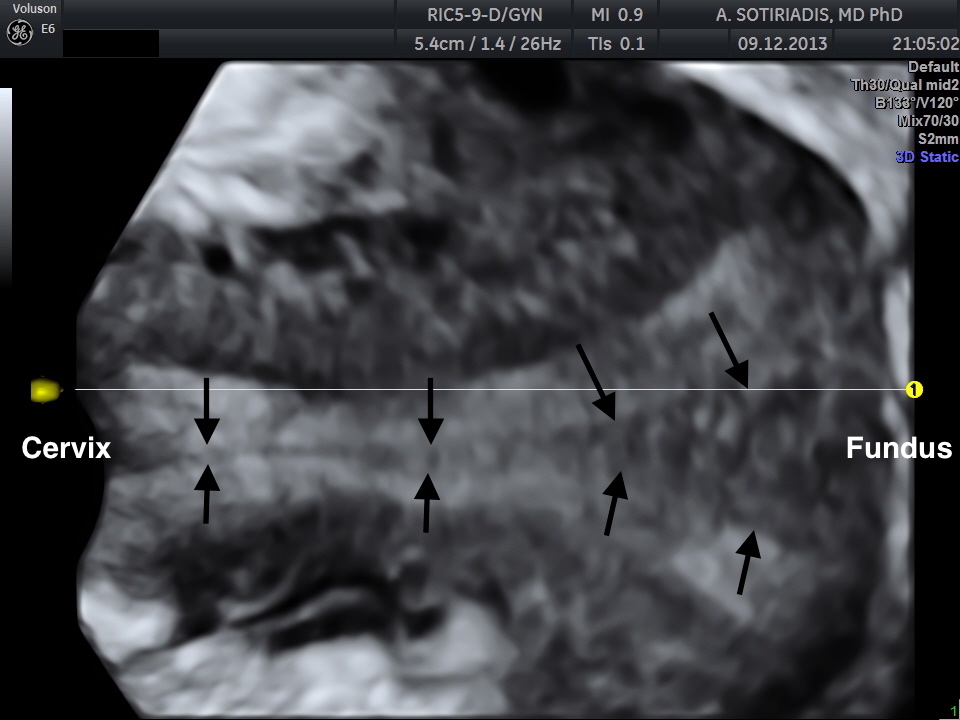

The patient was scanned on a GE E6 Voluson Expert machine (GE Healthcare, Milwaukee, WI), using a RIC5-9-D vaginal 4D probe. The uterus was originally scanned in a longitudinal plane and a 3D volume was taken. The reconstruction of the uterus on the coronal plane was done using the OmniView / Polyline modality and render modality with GYNSurfaceHD surface setting.

Three-dimensional reconstruction showed a midline septum running throughout the uterine cavity and the cervix, with normal contour of the uterine fundus. Therefore the diagnosis of a complete uterine septum as per the American Fertility Society, or a Class U2bC1 anomaly (complete uterine septum with septate cervix) as per the European Society of Human Reproduction and Embryology / European Society of Gynecologic Endoscopy (ESHRE/ESGE) new guidelines (3) was made (Figures 1 and 2).

In the case of complete septate uterus, 3D reconstruction of the endometrial cavity and the fundal contour in a coronal plane allowed the differentiation from uterus didelphys, which is the most common differential diagnosis when a double cervical os is encountered at speculum examination.